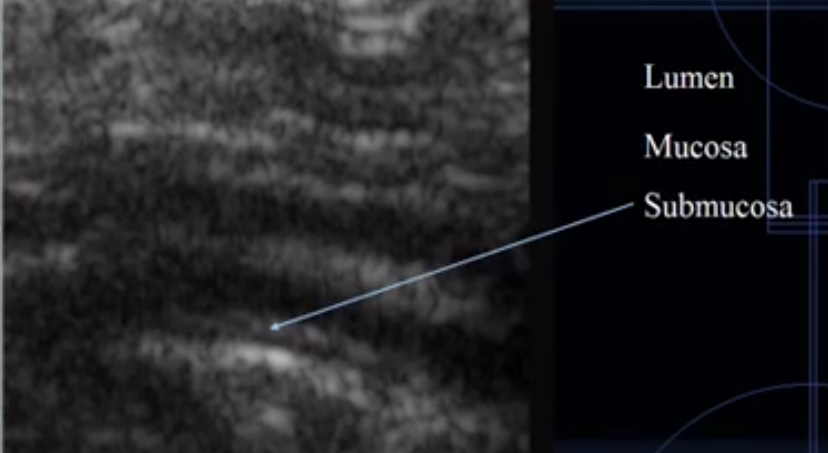

What does this image show?

Intestine

Which is the submucosa layer?